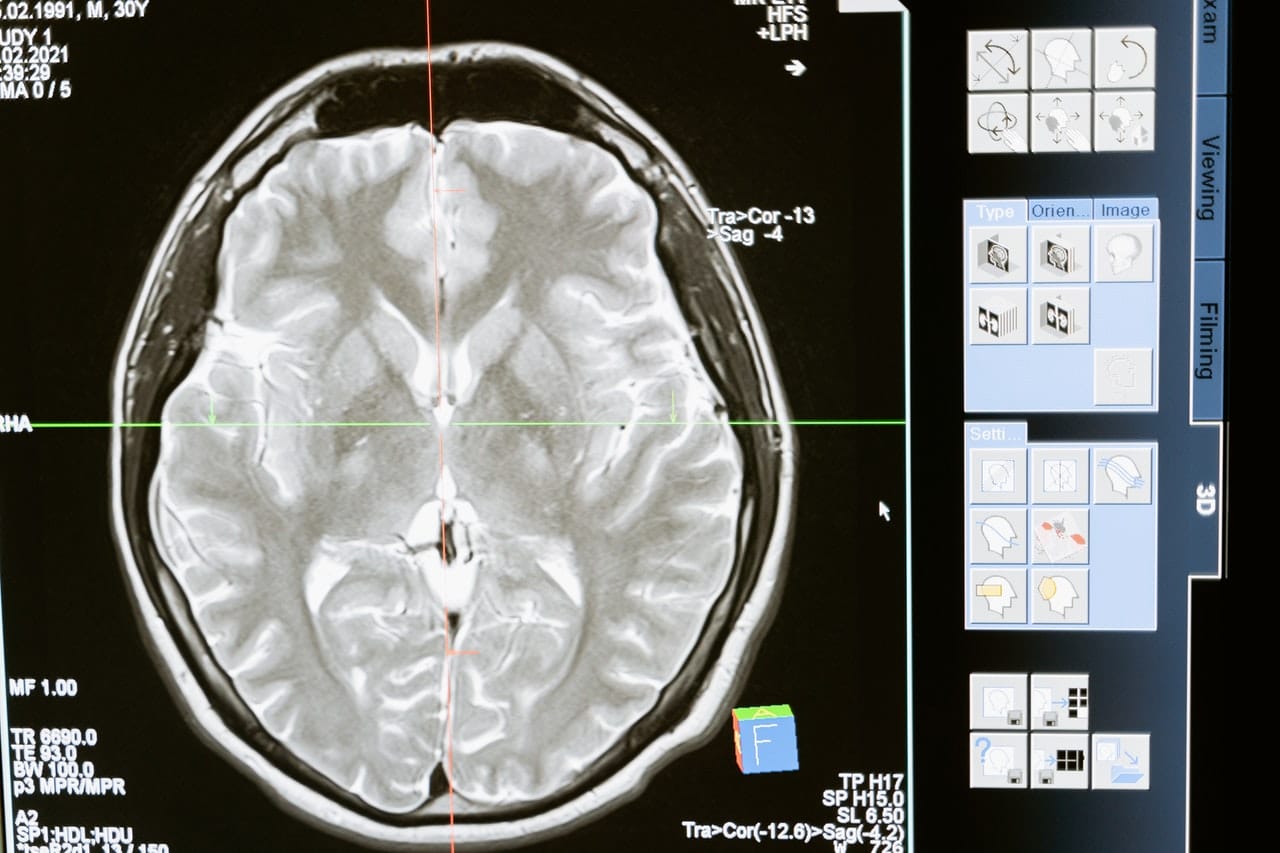

Hablamos de las desarrolladoras Ana Carrión y Nicole Álvarez, quienes presentaron el proyecto, “Localización del Núcleo Subtalámico, mediante el aprendizaje profundo del reconocimiento de imagen”. Recordemos que el Deep Learning está creando soluciones para múltiples industrias.